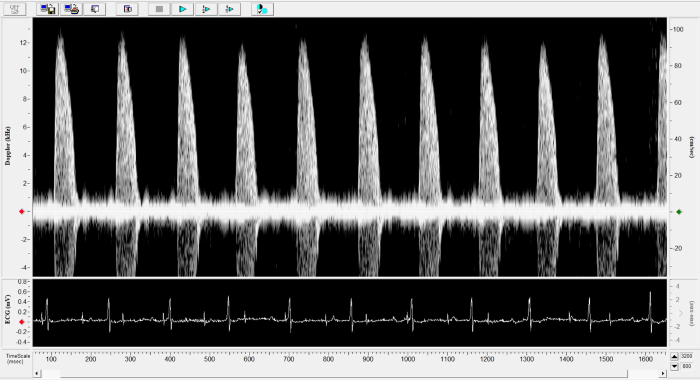

Renal Flow

Renal Flow. Image Credit: Scintica Instrumentation Inc.